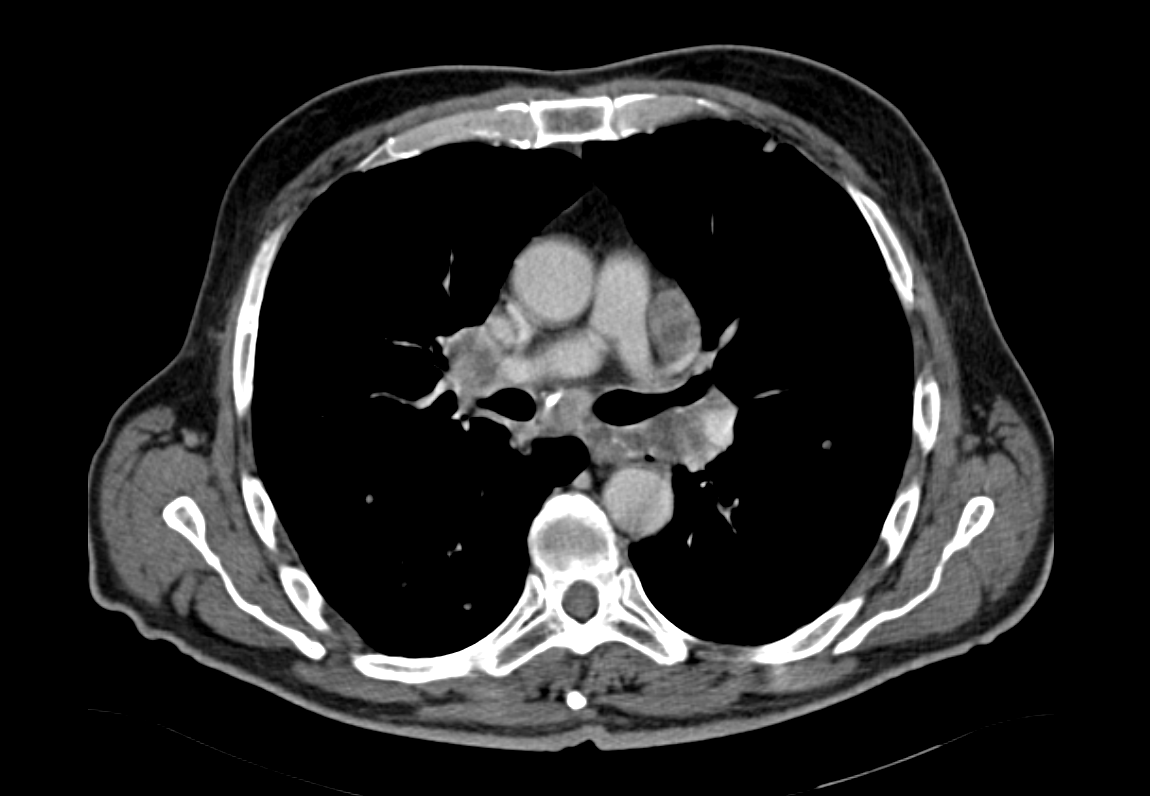

Αμφοτερόπλευροι πνευμονικοί όζοι ενδεικτικοί μεταστάσεων μελανώματος (Ευγενική παραχώρηση Dr. V. Penopoulos)